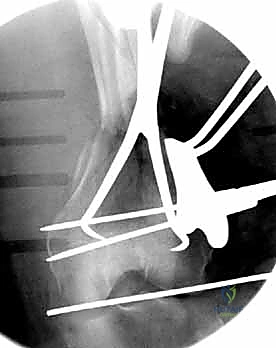

المرحلة الثالثة: إرجاع العظم (Reduction)

هذه هي الخطوة الأكثر أهمية. يقوم الدكتور هطيف بإعادة القطع العظمية المكسورة إلى مكانها التشريحي الأصلي. إذا كان الكسر ممتداً داخل المفصل، يتم تثبيت السطح المفصلي أولاً باستخدام مسامير دقيقة لضمان سطح أملس يمنع الاحتكاك والخشونة مستقبلاً.

المرحلة الرابعة: التثبيت النهائي بالشرائح والمسامير (Fixation)

يتم استخدام "شرائح الإغلاق التشريحية" (Anatomical Locking Plates) المصنوعة من التيتانيوم عالي الجودة. هذه الشرائح مصممة خصيصاً لتأخذ شكل الجزء السفلي من عظم الفخذ. يتم تمرير الشريحة أسفل العضلات وتثبيتها بمسامير تغلق داخل الشريحة نفسها (Locking Screws)، مما يوفر ثباتاً ميكانيكياً هائلاً، حتى في حالات العظام الهشة.